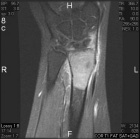

18 year old female with persistent and worsening wrist pain for four months